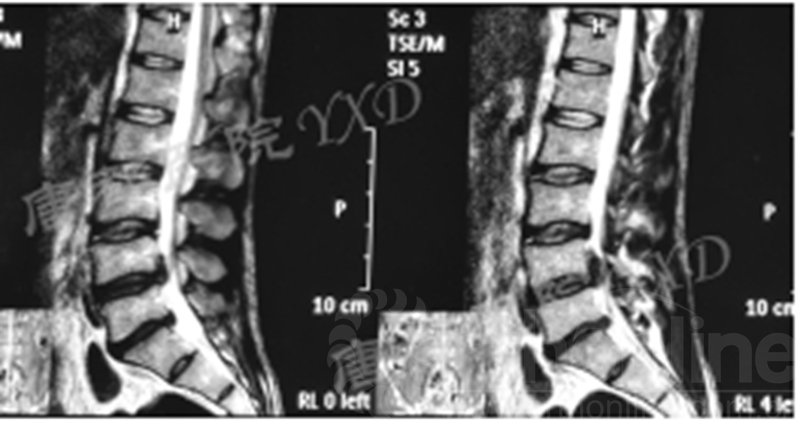

影像学检查:

诊断:腰椎间盘突出症术后复发

手术方案:显微镜辅助MI-TLIF腰椎翻修术